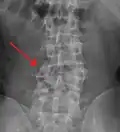

A burst fracture of L4 as seen on plane X ray A burst fracture of L4 as seen on plane X ray